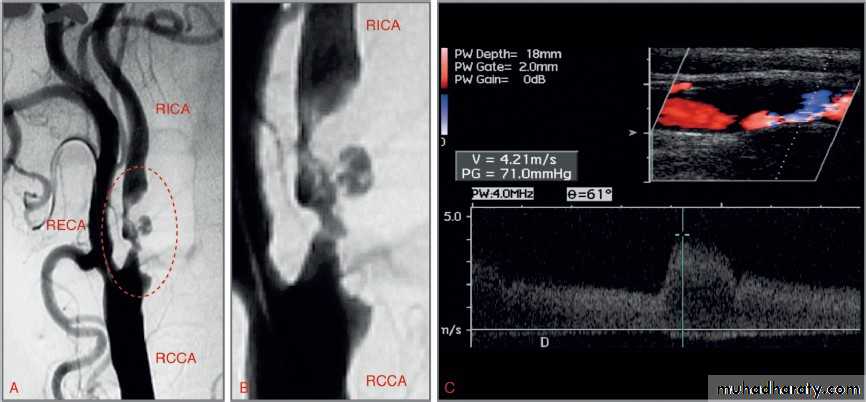

Shape of aneurysmAngiography of cerebral aneurysm